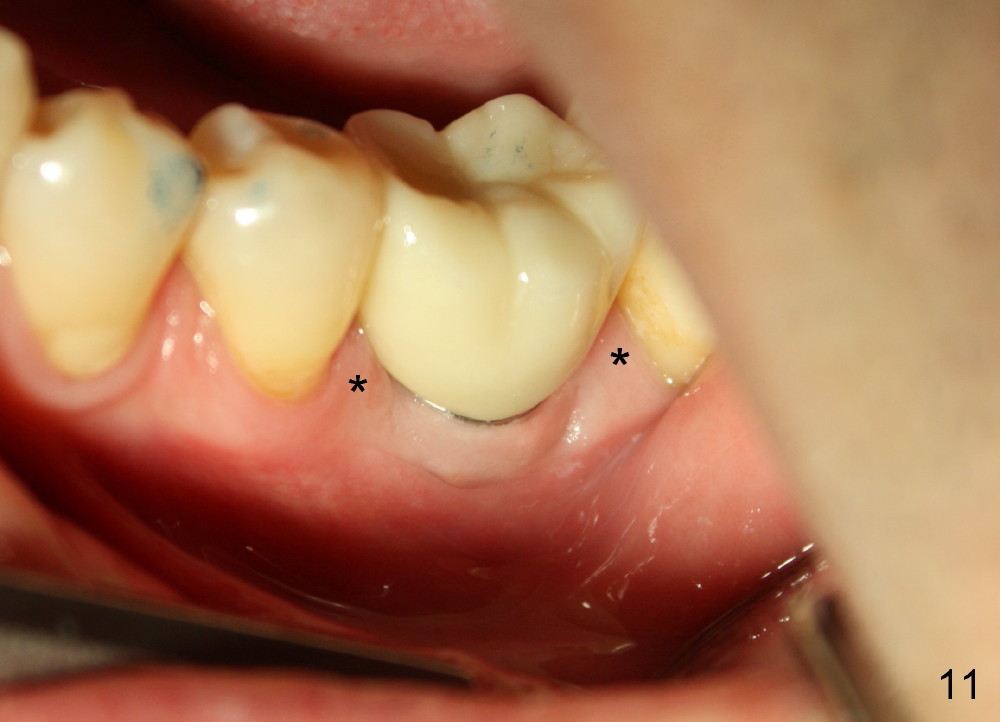

There is a thick gingival band buccal to the implant 7 months postop (Fig.9 *). Osteointegration occurs (Fig.10). The most unexpected finding is the formation of the papillae (Fig.11 *) when the permanent crown is seated. The cosmetic result is due to immediate placement of the large implant. Delayed implant usually cannot achieve this type of outcome.